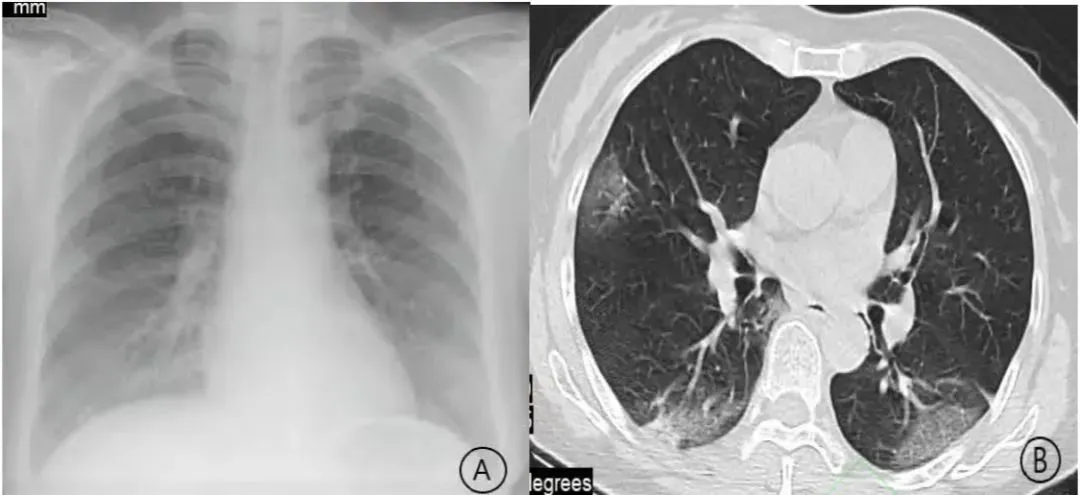

但是最近却出现了很多“白肺”患者,转阴后一直咳嗽、气短、胸闷的,特别是有基础疾病的要特别小心,一定要记得去医院拍个肺部CT,可能会出现危重症。